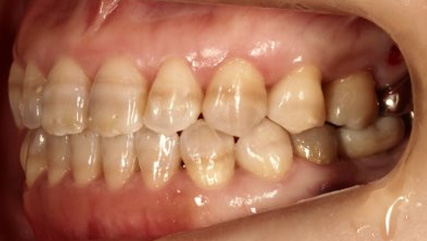

治療前

治療終了前

下顎が上顎より前に出ている状態です。お顔つきも、下顎の先(オトガイ)が前に出ているような横顔になる場合が多いです。前歯が咬んでいないことが多く、奥歯への負担が大きい状態になります。そのままのかみ合わせを続けてしまうと、奥歯がかけたり、割れたりするリスクが高まります。歯列矯正では奥歯の位置をコントロールし、前歯のかみ合わせを作る治療方針を立てます。ごく稀に、歯列矯正ではかみ合わせを作れない場合もあり、その場合は外科矯正という手段を用いて矯正治療をしなければいけません。受け口は、遺伝性が強いとも言われておりますので、そういった情報も考慮し、治療を進めていくことが大切です。

前歯が咬んでいない状態を言います。受け口同様、奥歯への負担が大きく、歯を失いやすい不正咬合と言われております。インビザラインでの治療の方が、ワイヤーを用いた治療より治療しやすい症例が多く、治療期間はワイヤー治療に比べて比較的短期間になることが多いです。出っ歯、同じように口呼吸、舌の位置が悪い、口が閉じれないなどの症状を伴うことが多いので、そういった点も考慮して治療していく必要があります。